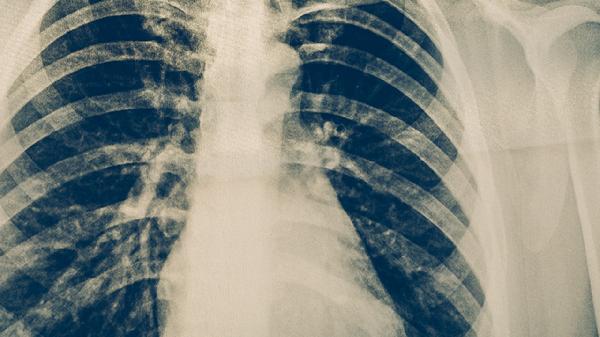

空洞肺结核治愈后影响寿命吗

空洞肺结核治愈后通常不会影响寿命,但需定期复查并保持健康生活方式。空洞肺结核是肺结核的一种严重类型,治愈后肺功能可能部分受损,但通过规范治疗和后续管理,多数患者可恢复正常生活。

空洞肺结核治愈后若未遗留严重并发症,如广泛肺纤维化或慢性呼吸衰竭,一般不会缩短预期寿命。规范抗结核治疗可有效杀灭结核分枝杆菌,病灶愈合后空洞可能闭合或形成纤维瘢痕。患者需避免吸烟及接触粉尘,预防呼吸道感染,适当进行有氧运动帮助肺功能恢复。饮食应保证优质蛋白和维生素摄入,如鸡蛋、瘦肉、西蓝花等,促进组织修复。